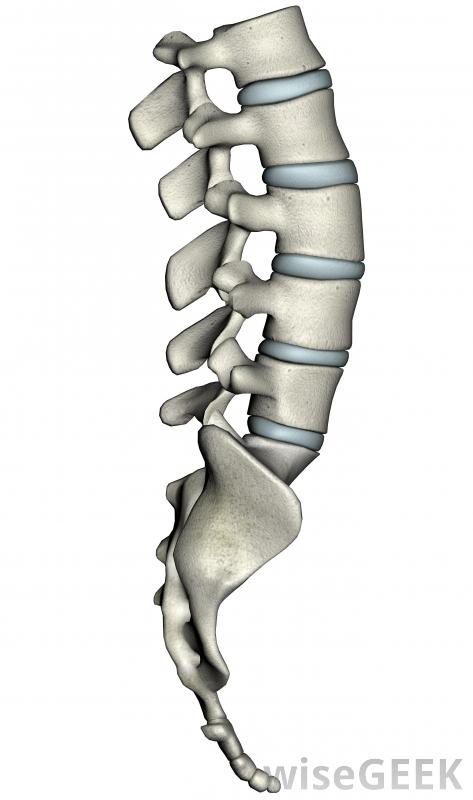

脊柱融合术是一种将两个或两个以上的椎骨(脊柱中的骨头)连接在一起的一种医疗方法。它用于治疗各种各样的脊柱损伤,成功率很高。脊柱由33个椎骨组成,其中24个是分开的。将这些椎骨融合在一起,可以使用许多不同的技术。但是,所有这些技术都依赖于相同的基本原理。

启动脊柱融合,在需要融合的椎骨所在的位置开一个切口,如果是颈部的椎骨,这个切口通常是从前面切的,如果是背部中下部的椎骨,切口是在背部进行的。然后在椎骨之间放置一小块骨头。随着时间的推移,椎骨会将自己移植到这块骨头上,最终形成一个坚固的结构。螺钉或金属板等辅助设备可能用于也可能不用于脊柱融合,通常只有在脊椎需要时才会使用当植骨时用来固定它们的夹板。

进行脊柱融合手术的一些原因是:脊椎运动引起的慢性疼痛,椎间盘问题,脊柱畸形和脊椎骨折。偶尔脊椎会发生小骨折,使骨脱离正常位置,并与另一根椎骨摩擦。这是一种非常痛苦的情况,称为脊椎滑脱,脊柱融合是一种相对容易的止痛方法。

在脊柱出现不规则的情况下,例如相当常见的s形脊柱侧凸,脊柱融合术可以帮助脊柱恢复到正常的形状。由于脊柱侧凸并不是非常有害,脊柱融合术通常只用于弯曲变得非常大或似乎正在迅速恶化的情况下。